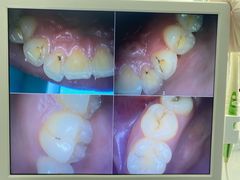

• 牙博士口腔品牌连锁(杨浦店)

• -牙博士口腔品牌连锁(杨浦店)

1111英 | 25-07-17